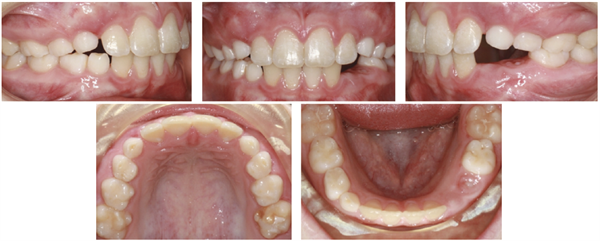

Intraoral examination confirmed an Angle Class I dentofacial pattern with several complex clinical conditions (Figs. 2–3):

• Complete posterior buccal crossbite on the left side; the left maxillary posterior teeth fully overlapped the mandibular buccal segment with no functional contact

• Constricted mandibular arch with the lower left posterior segment lingually tipped and collapsed

• Lower dental midline shifted to the right

• Mild maxillary spacing in the anterior region (U2–2)

• Mild mandibular crowding

• 20% overbite with moderate overjet

Fig. 2: Initial intraoral views (right lateral, anterior, left lateral) demonstrating the complete buccal crossbite on the left side and upper anterior spacing.

Fig. 3: Initial occlusal views (maxillary and mandibular) showing mild upper spacing and the constricted, lingually displaced lower left posterior segment.